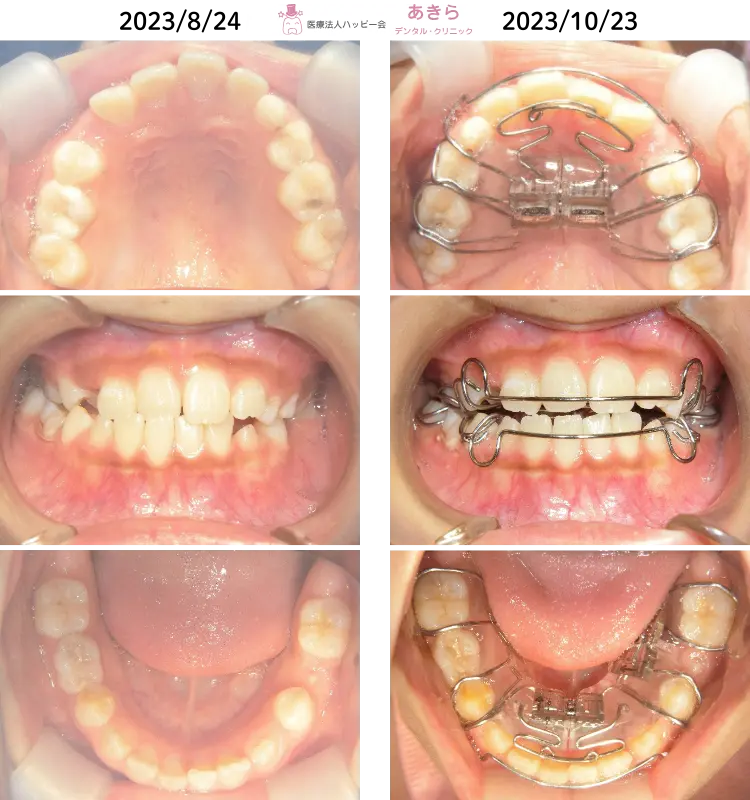

2023年8月24日 初診時口腔内 ⇒ 10月23日 SHAスタート時

- 2023年10月より SHA(SH装置)スタート